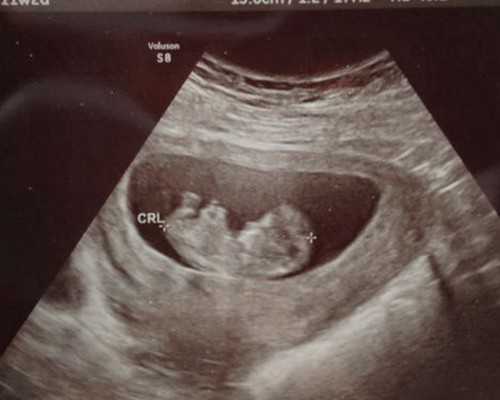

胚胎移植14天后,抽血验孕,一般当天可以完成,如未怀孕则要等待下次移植,这部分只需要挂号和验孕的费用在100元左右。